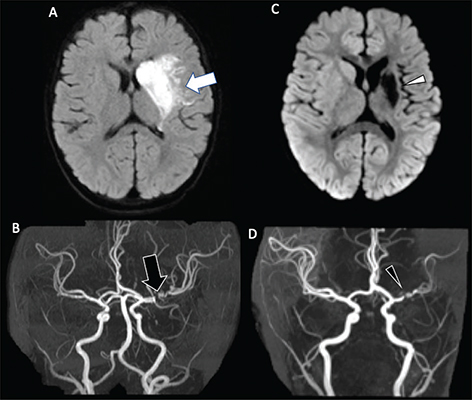

MRA can help define the site of stenosis, helping narrow the diagnosis in patients with arteriopathy, or identify a large vessel occlusion (Figure 4) (17, 23, 95, 96). A “banding” pattern is considered a pathognomonic feature for FCA-i but is less commonly identified by CTA or MRA than catheter angiography, presenting in less than one-quarter of cases, and is therefore specific but not sensitive for the diagnosis (Figure 5) (30). If arteriopathy is suspected and MRA is equivocal, vessel wall imaging, utilizing black-blood, T1-weighted volumetric imaging after gadolinium can demonstrate abnormal vessel wall enhancement in the setting of active inflammatory processes, as well as assess for intracranial arterial dissection on pre-contrast T1-weighted imaging (69). Between 64% and 74% of arterial defects in pediatric ischemic infarctions are located in the supraclinoid carotid artery or M1 segment of the middle cerebral artery (70). Stenosis in FCA may change in appearance over the short term. Over the long term, they usually normalize (~25%), stabilize after improvement (32%), or stabilize (45%) without further infarctions (23, 24). Outcome is better in patients in whom the arteriopathy stabilizes or improves than in those in whom it progresses, with a high risk of recurrent stroke in the latter population, approaching 25% within 1 year (17, 24). Some genetic arteriopathies have unique imaging appearances, such as ACTA2 mutation, which demonstrates dilation of the proximal internal carotid arteries, occlusion or narrowing of the distal internal carotid arteries, straight “broomstick-like” arteries of the circle of Willis, and absence of lenticulostriate collaterals (Figure 6) (34).

Fig 6

Figure 6. ACTA2 Mutation. Axial ADC (A) demonstrates reduced diffusivity in the periventricular white matter, compatible with acute infarct. 3D Time-of-Flight MRA (B) shows enlargement of the internal carotid arteries (arrowheads) with narrowing of the distal internal carotid arteries (arrow). Follow-up axial T2-weighted image (C) shows evolution of the infarct to cystic encephalomalacia. Case courtesy of Dr. Tamara Feygin, Department of Radiology, Children’s Hospital of Philadelphia.